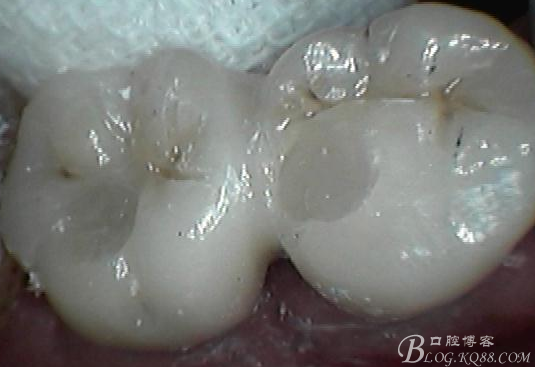

牙齦封閉良好,咬合,近中觸點(diǎn)穩(wěn)定

樹脂封閉螺絲孔